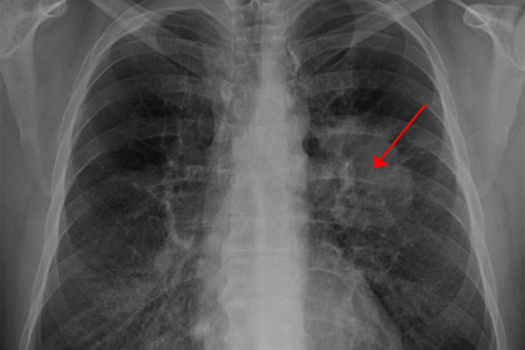

Исследователи показали, что при немелкоклеточном раке легких возникают мутации, которые усиливают активность белка NRF2, способствующего образованию антиоксидантов. При этом уменьшается количество молекул, участвующих в производстве активных форм кислорода и вызывающих окислительный стресс. Некоторые из этих соединений расщепляют белок BACH1. Однако при увеличении содержания антиоксидантов BACH1 оказывается защищенным и помогает раковым клеткам распространяться.

Кроме того, ученые пришли к выводу, что витамин Е, включенный в состав пищевых добавок, также увеличивает вероятность распространения рака легких посредством своего влияния на BACH1.